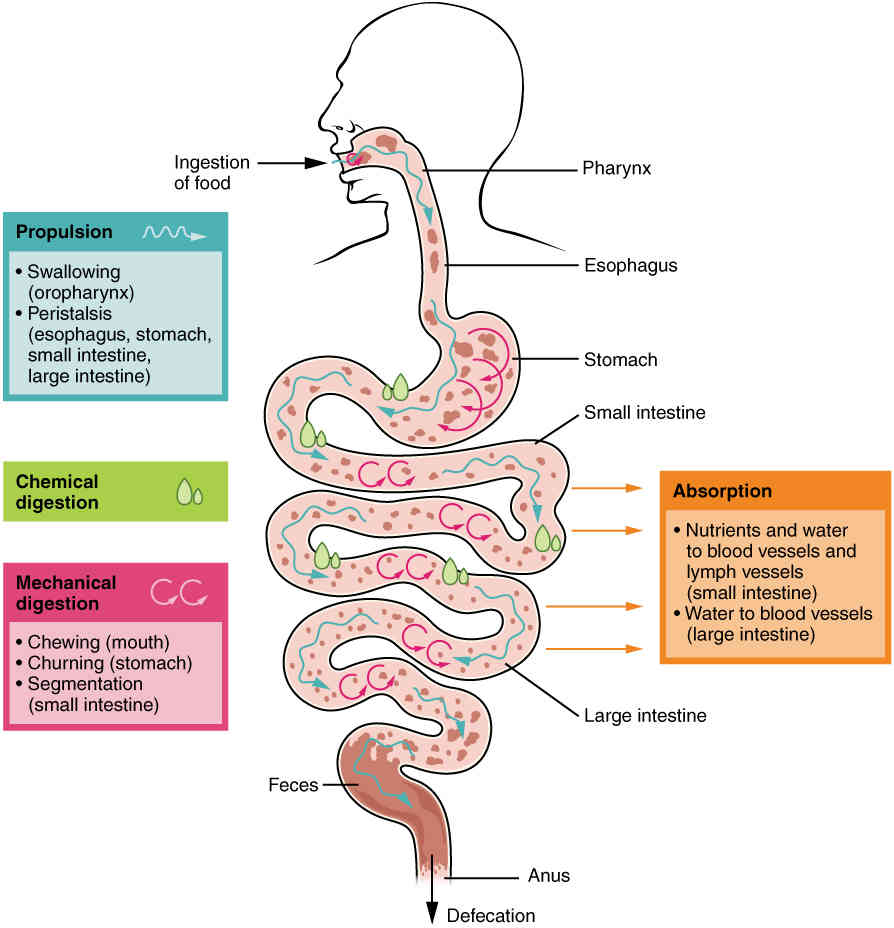

This page is under construction. For now, it is just a resource of the images found in the OpenStax Anatomy and Physiology Handbook. It wil slowly change into a revision tool. Each slide has a number. Use this to refer to the slide. When completed, it will have an unlabelled section, with labelled slides in parallel. On the unlabelled slides, write your answer and use the labelled slide to assess yourself. Keep track by also noting the number on each slide. Improvement at each attempt is important, more so than full marks on a first attempt.